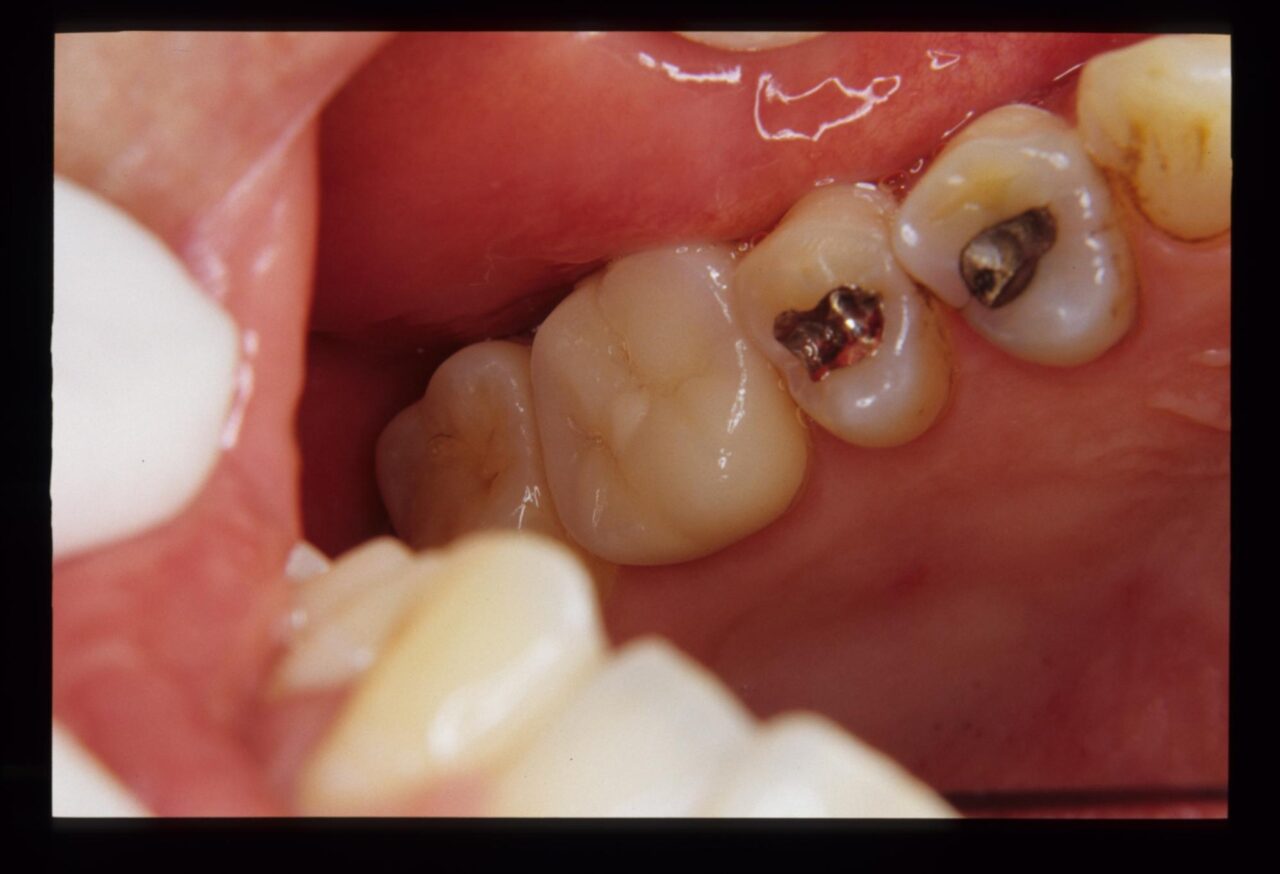

患者は医療従事者で、噛むと違和感があると訴えていたので、取り敢えず術前の修復物を除去してフルクラウンの仮歯を装着して様子を診ていたが、自発痛が出てきたために抜髄処置を行うことになりました。

麻酔をした後にラバーダム防湿を行い、随腔内(神経がある空間)を探索すると健全な歯髄(歯の神経)は診られず、腐敗した組織が確認できます。